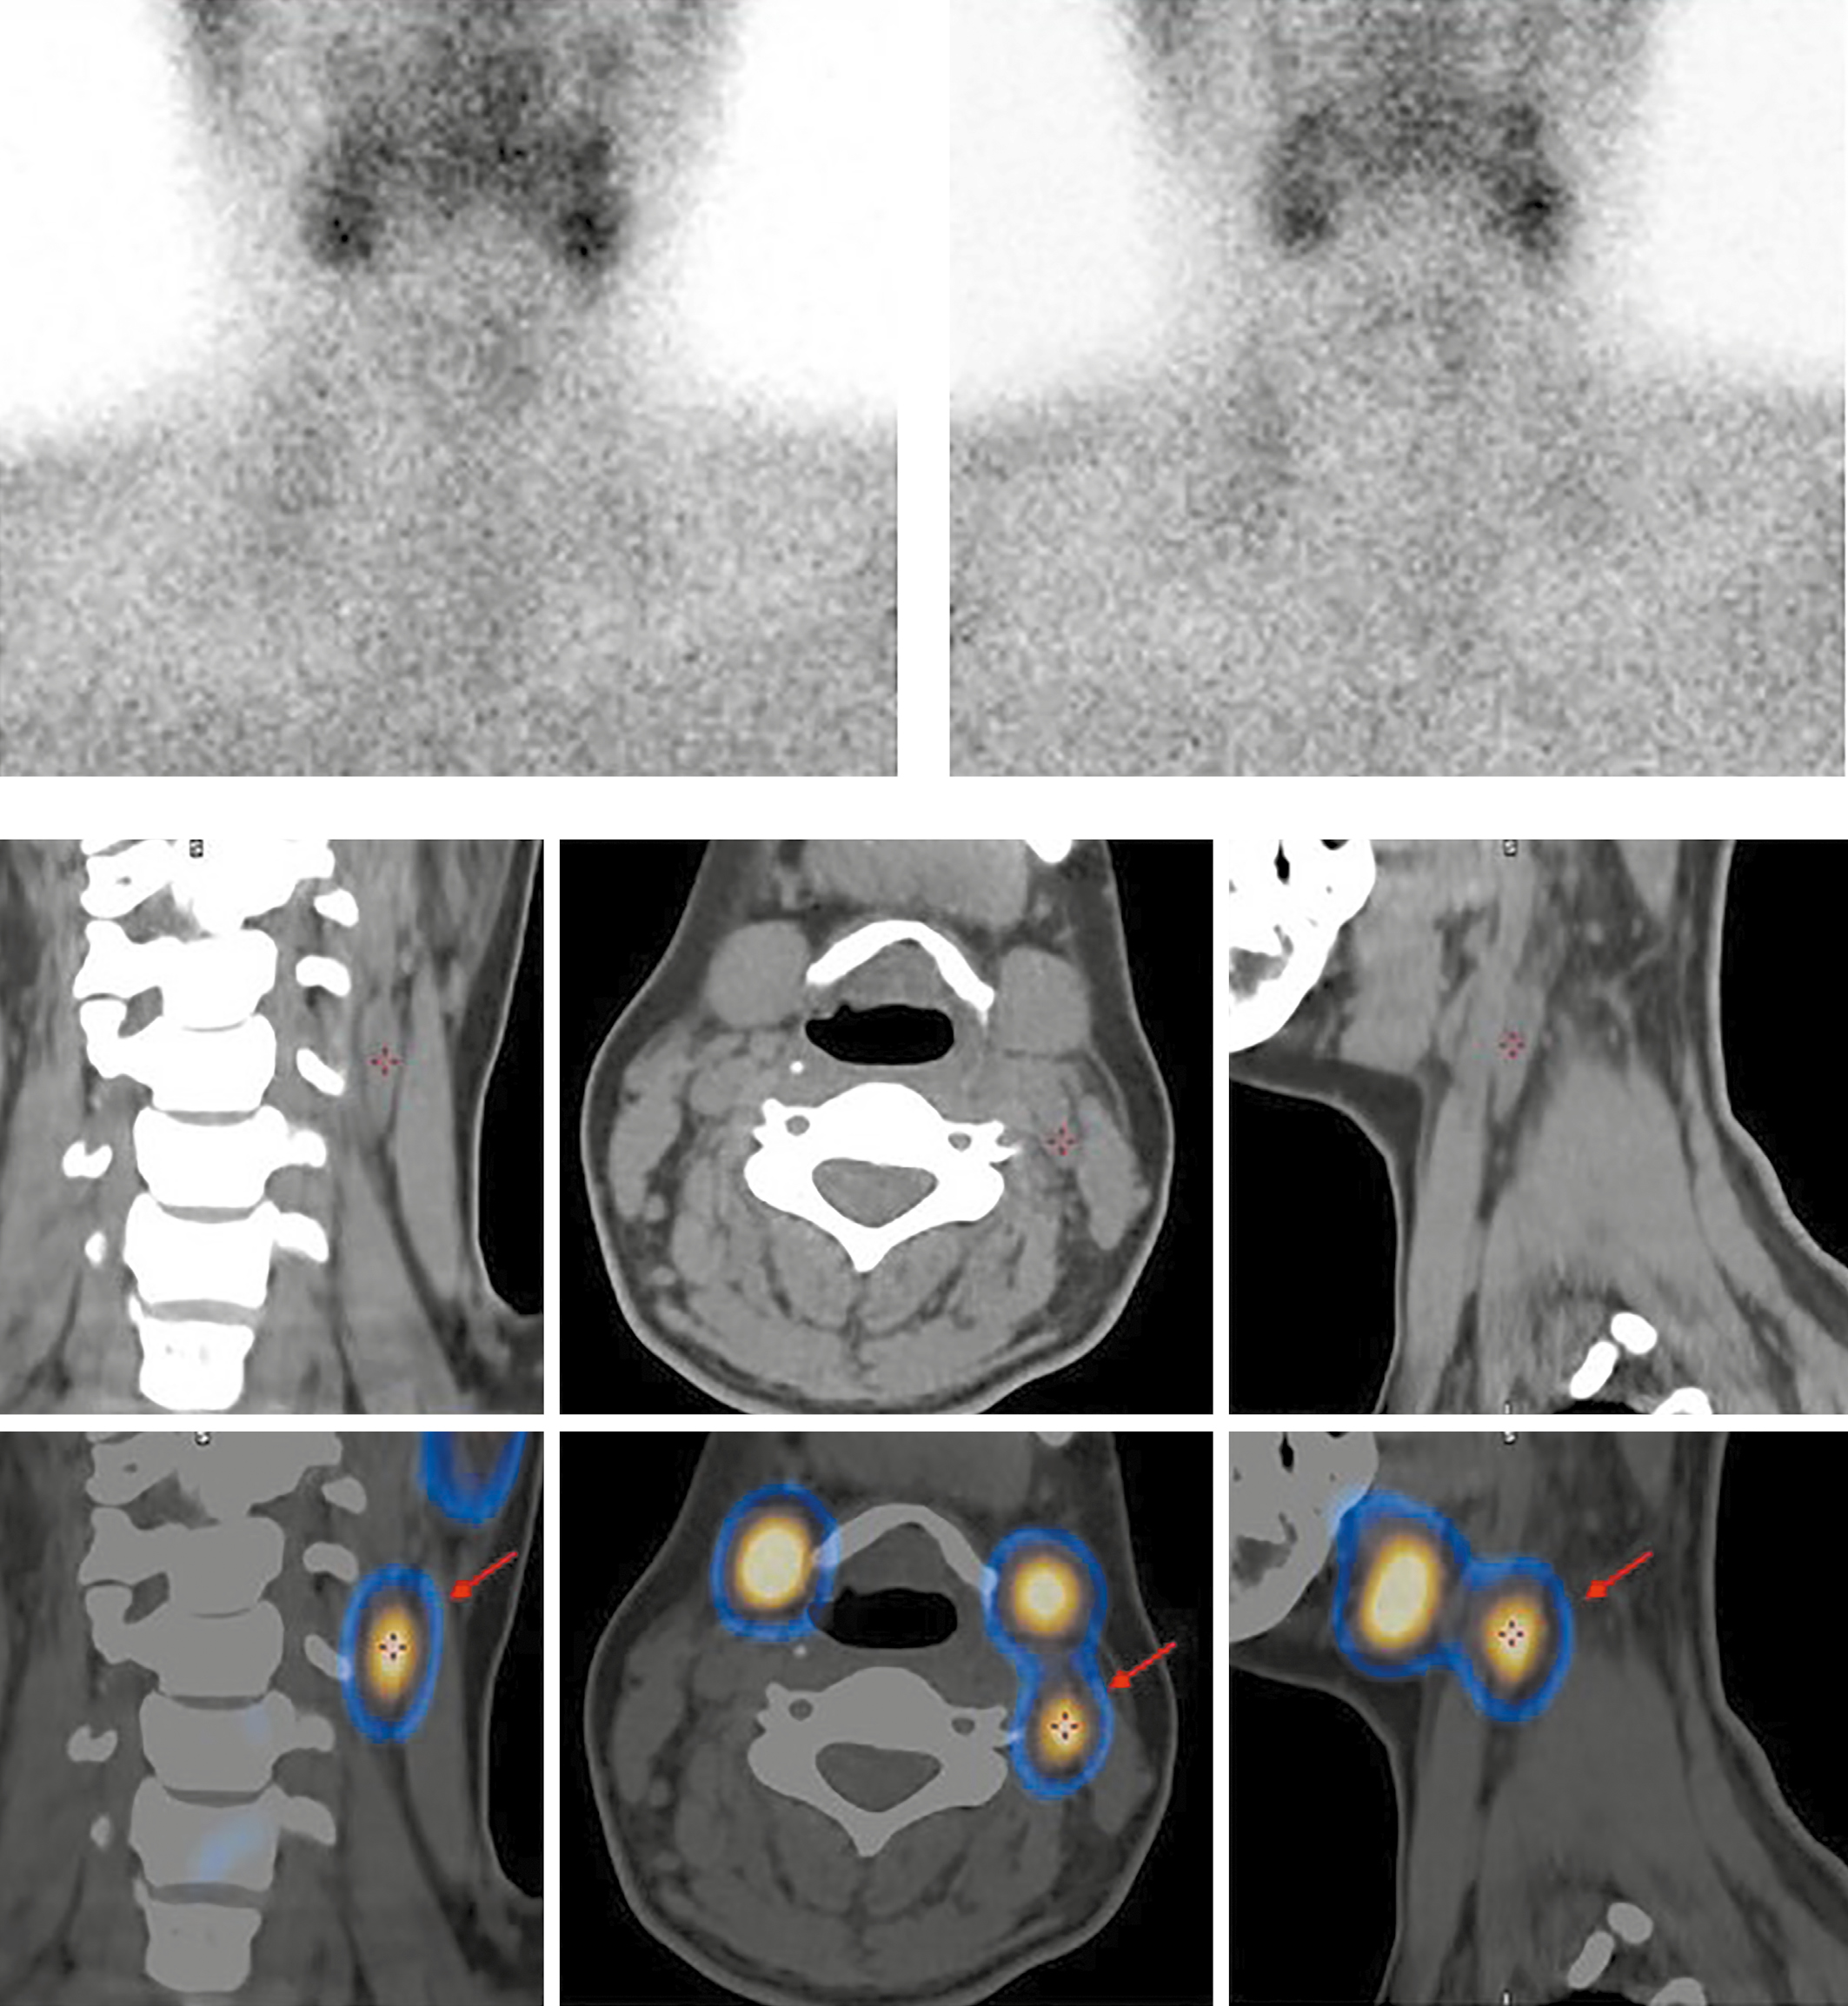

2. Рисунок 2. Верхний ряд — планарная сцинтиграфия через 15 и 90 минут после введения РФП. Нижний ряд — ОФЭКТ-КТ через 90 мин. | |